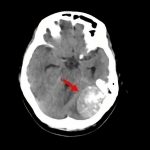

病名

断層撮影

手術前2